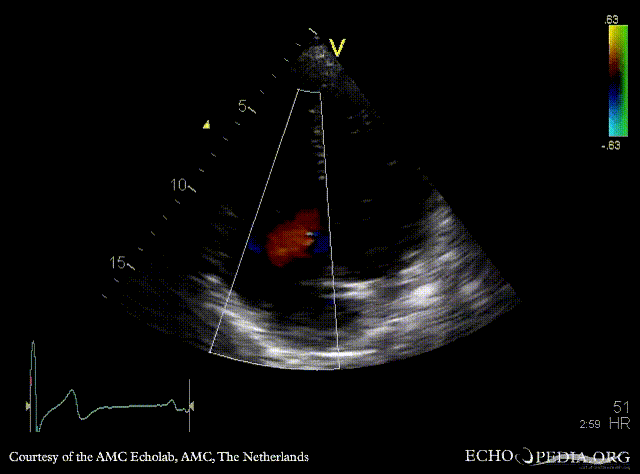

Severe pulmonary regurgitation

PSAX: Color Doppler, severe pulmonary regurgitation Continuous-wave signal of transpulmonary flow